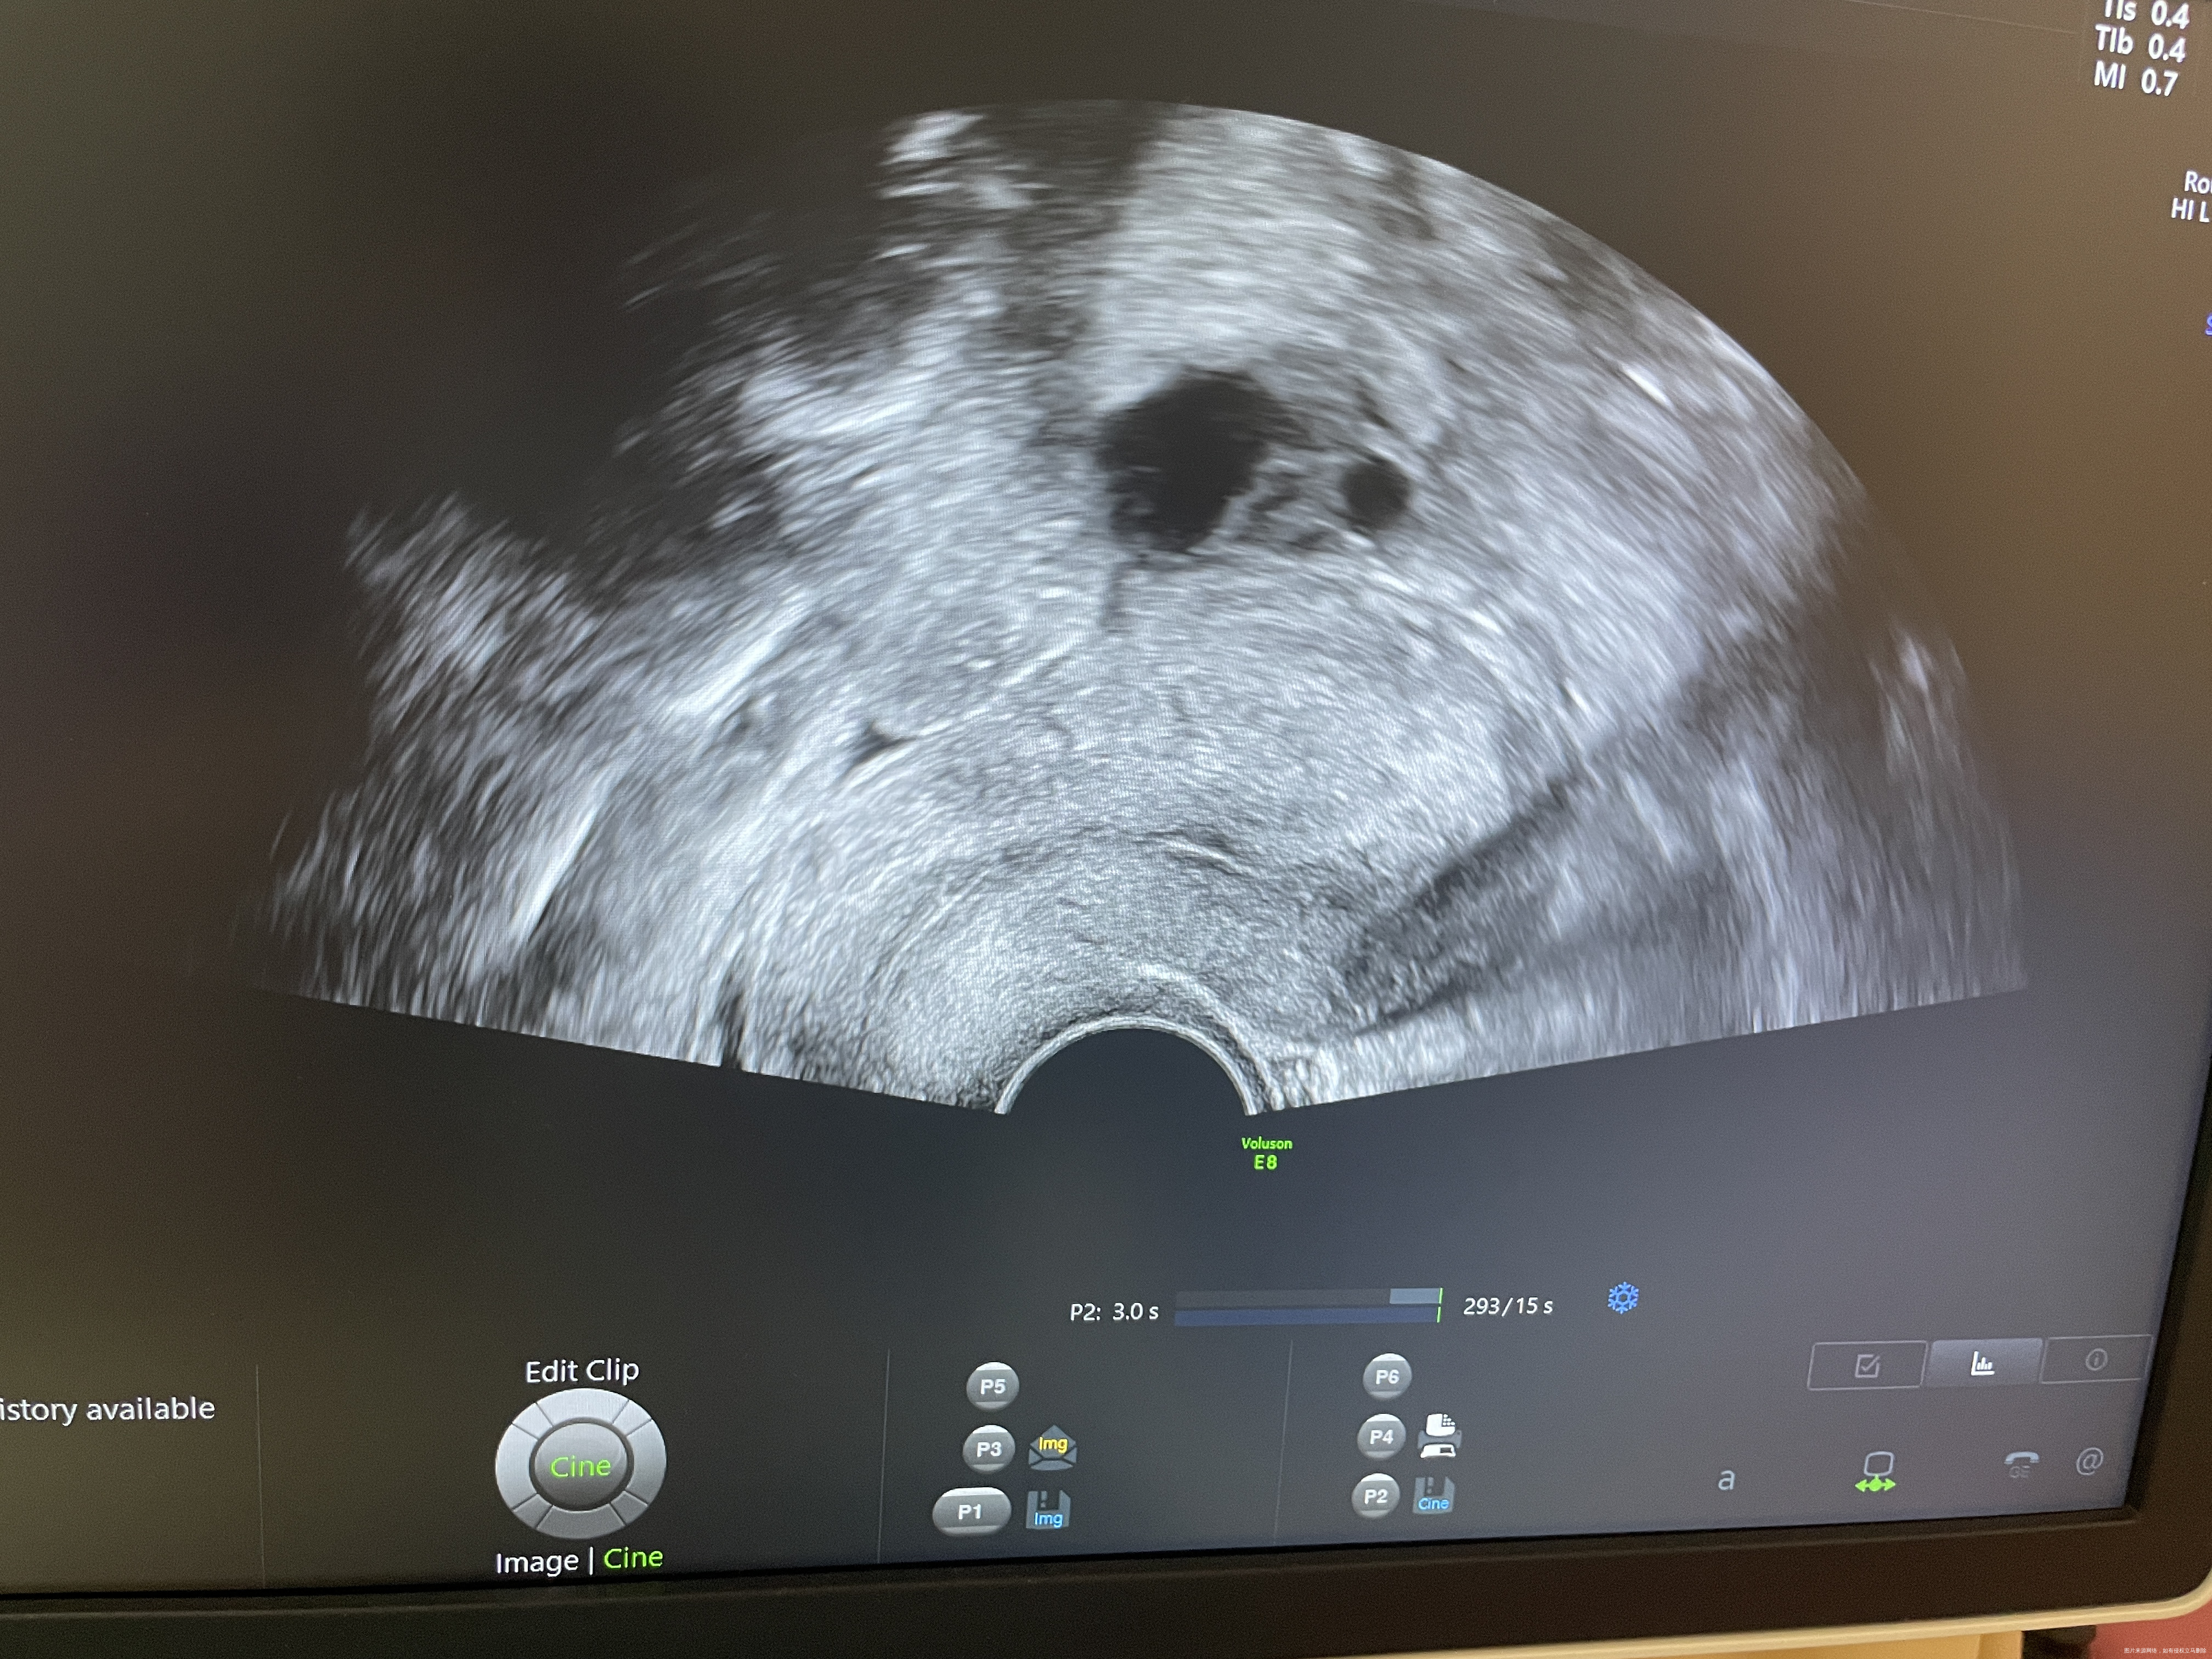

请问医生这个内膜适合移植不

一般内膜≥8mm,形态呈三线征,更有利于胚胎着床。

内膜线还可以,就是不知道厚度怎么样?听生殖医生的安排就可以啦!

首先,你提供的是月经第几天的超声?凭这张超声显示内膜比较薄,只见到宫腔线,如果是最厚的时候,是不适合移植的

马琴 回复 李玉香:月经第14天的

李玉香 回复 马琴:如果月经周期规律,那么内膜需要处理后再移植

这个没有标记内膜厚度,看上去不厚,最好8-14cm

马琴 回复 周加林:月经16天单子是10

你好,内膜厚度8到14mm都很适合着床的。